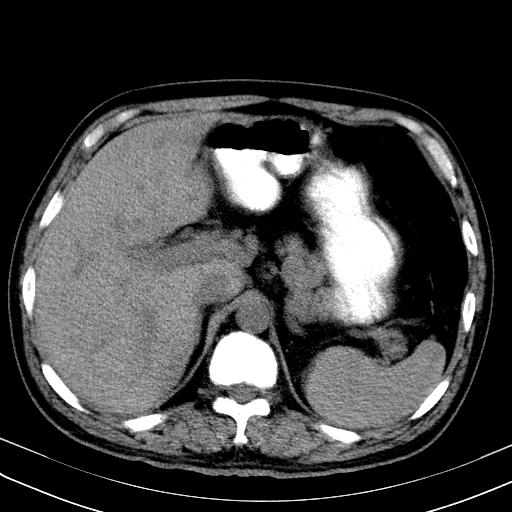

先行ct平扫,纵膈内多发软组织影,ct值约为36hu,以下为增强扫描和腹部平扫。

经典?纵膈多发肿大淋巴结。腹膜后未见异常。

1)考虑淋巴瘤。2)双侧少量胸腔积液。

大家看看肝脏右叶片状低密度影是什么改变啊?